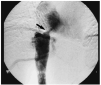

Enfermedades vasculares hepáticas